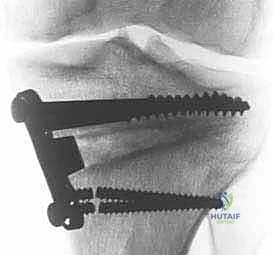

باستخدام أدوات دقيقة ومناشير جراحية متطورة، يتم عمل قطع غير مكتمل في عظمة الساق. هناك طريقتان رئيسيتان:

* الشق المفتوح (Opening Wedge): يتم فتح العظم من الداخل وإضافة طعم عظمي (صناعي أو طبيعي) لملء الفراغ وتعديل الزاوية. وهي الطريقة الأكثر شيوعاً حالياً.

يتم فتح العظم تدريجياً وببطء شديد حتى الوصول إلى الزاوية التي تم حسابها في التخطيط الرقمي قبل الجراحة.